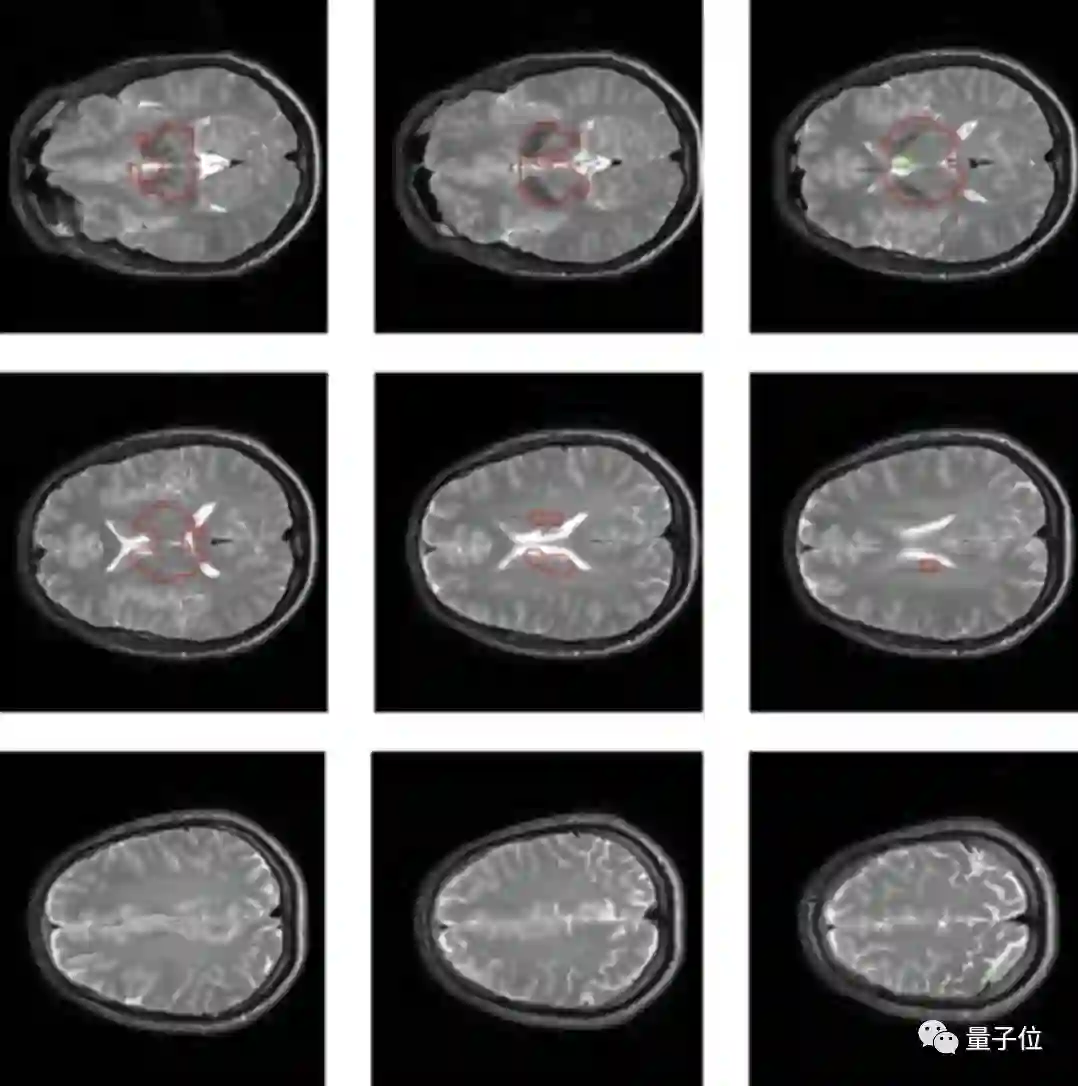

具体来说,这项研究采用了一种基于多量子相干的磁共振成像方法。

磁共振成像能基于核磁共振原理,检测构成物体原子核的情况,进而推断组成物质的分布、种类、数量、化学环境等,据此绘制成整个物体内部的结构图像。

通过这种方法,在测量了40个人(18~46岁之间)的大脑信号后,研究人员在大部分人的大脑区域中都测量出了一种诱发脑电信号。

这类信号有点像心跳诱发脑电位信号(HEPs,大脑感应心跳的信号),都依赖于大脑意识的产生,主要与短期记忆与意识感知相关。

然而正常来说,基于多量子相干的核磁共振根本没办法检测到诱发脑电信号,因为这些信号与任何经典的核磁共振信号都没有相关性。

对此研究人员推测,这一现象用量子纠缠解释是最合理的,进一步来说,这也意味着这些大脑功能与量子计算相关。